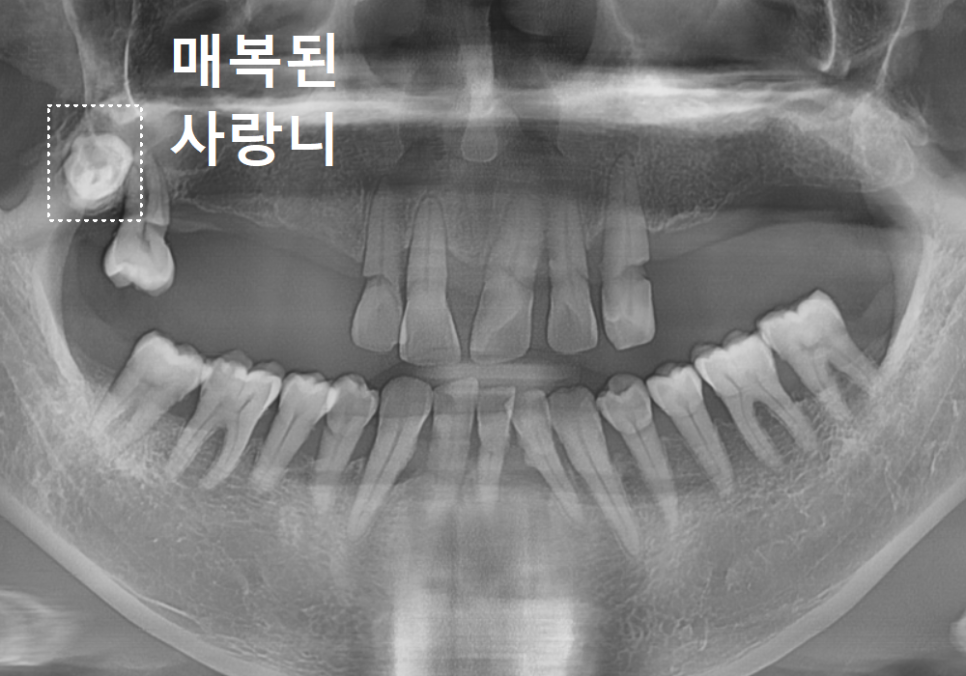

환자분의 구강 상태를 보여주는

파노라마 사진이에요.

언뜻 보셔도 치아가 몇 개 남지 않았다는 걸

금방 아실 텐데요.

위턱과 아래턱 모두 치아가 많이 빠져있고,

그나마 남아있는 치아들도 상태가 좋지 않았습니다.

치아를 잡아주는 잇몸뼈(치조골)가 많이

녹아내려 있었거든요.

특히, 틀니 고리가 걸리는 치아들에

너무 많은 힘이 쏠리다 보니,

뿌리 쪽이 심하게 패어

몹시 약해진 상태였습니다.

이렇게 되면 틀니를 아무리 새로 맞춰도

잇몸만 아프고 제대로 씹기가 참 힘듭니다.